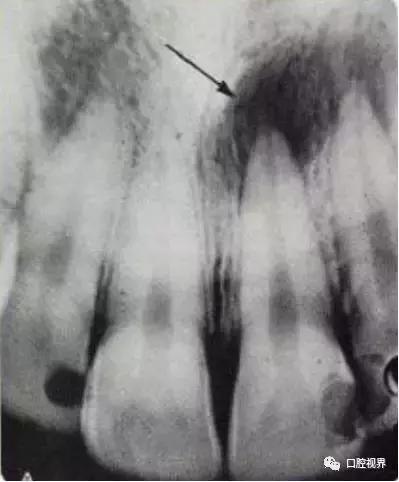

对于简单的龋齿牙医们通常的办法就是补牙。一般在补牙前,医生了解你的病史,有无自发痛,或者只有冷热刺激痛,是简单的龋齿还是牙髓炎心里大概就有谱了,再拍张片子看看根尖有没有低密度影,有没有骨质破坏吸收,来选择怎么治疗。